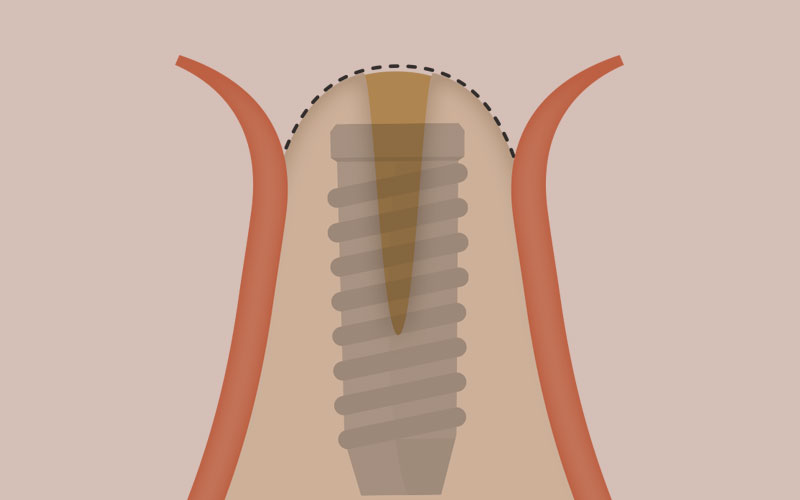

インプラント治療で取り戻した歯は、ほとんど天然歯と同じように見えますが構造に違いがあります。インプラントは、歯の根の代わりになる「インプラント本体」、歯の代わりになる「被せ物」、そしてその両方を繋ぐ「接合部」が合わさって人工の歯を作り直します。

インプラントという人工の歯の根を、歯を失った箇所のあごの骨に埋め込み、骨と結合させます。

埋め込んだインプラントを土台として、人工の歯を設置し、歯の見た目と機能を回復します。

インプラントそのものはチタンで出来ています。歯の根と同じように約10mm程度の長さをしているチタン製の人工物が、歯の根の代わりにあごの骨に埋め込まれます。

インプラント体の素材であるチタンには、時間の経過とともに骨と一体化して固まってしまう性質があり、この作用を利用して、人工の歯の根をしっかりと固定させています。インプラントはネジの様な形状で溝が刻まれており、スクリューさせてあごの骨にしっかりと埋め込めるようになっています。またインプラントのメーカーごとに、より良く骨と結合させるために工夫が凝らされた表面形状で作製されており、これがメーカーごとの大きな性能の違いとなっています。